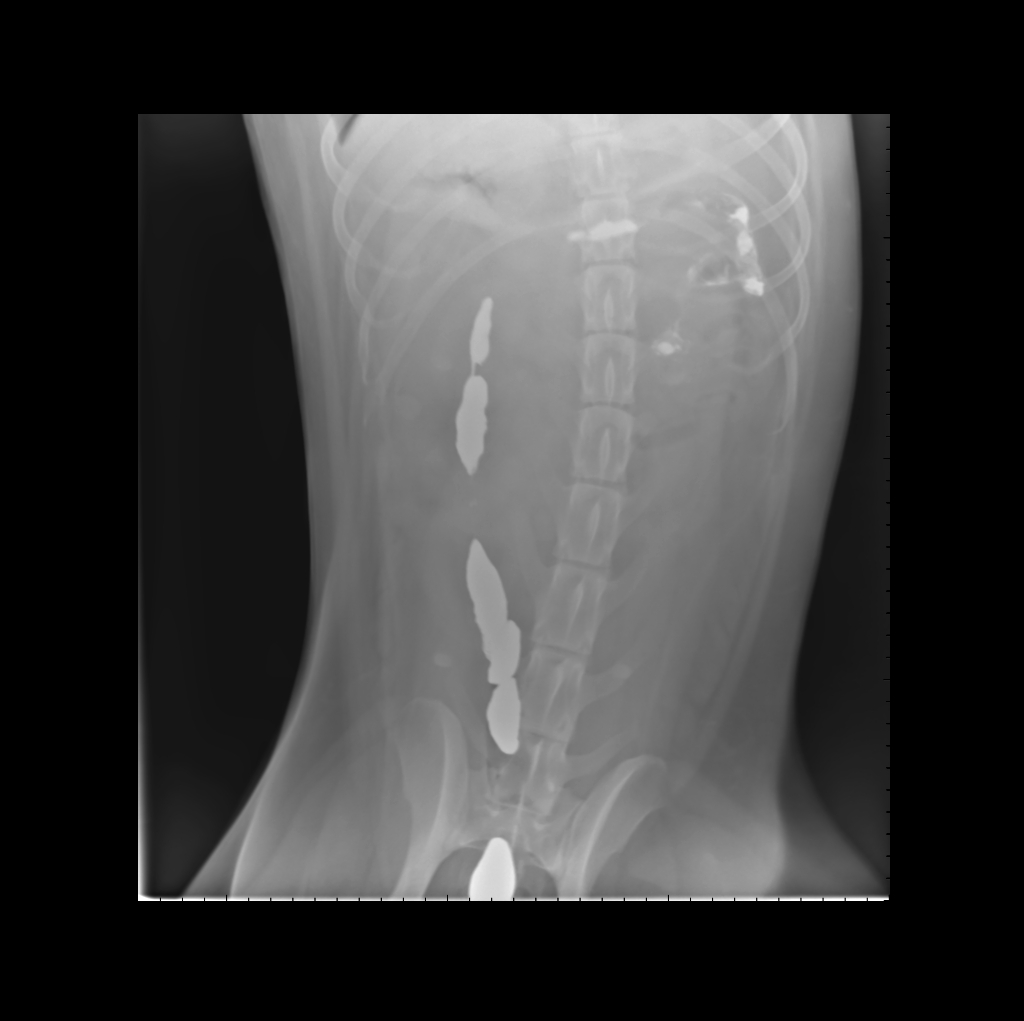

犬呕吐怀疑胃肠梗阻X线造影后8小时正位片造影剂进入结肠